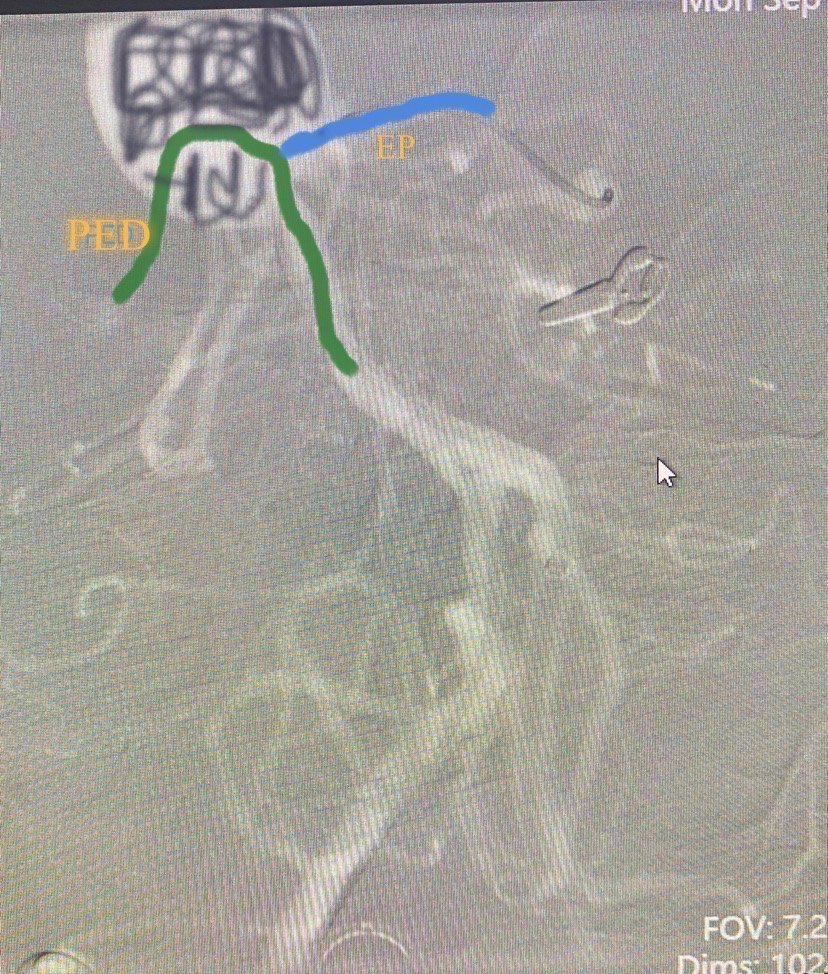

那么改变一下思路,将绿色的普通支架换成血流导向装置,蓝色普通支架呈T形放置,瘤腔内疏松填圈,理论上似乎更为合理。如示意图(画图水平超烂,见谅)。

然后填圈至动脉瘤中、上部致密填塞,下部近分支处疏松填塞,同时释放左侧EP2支架,尾端紧贴pipeline侧方呈T形放置。最后稍推拉完全pipeline至基底动脉中下段。(这是本次手术有瑕疵的地方,尾端覆盖基底动脉稍长了一些,与我们测量计算误差有关)

后记:关于血流导向装置联合T形支架技术(Flow-T stenting)治疗基底动脉尖动脉瘤,目前尚无文献报道,但Flow-T stenting这项技术的发明和命名不是我们的原创(详见下图),但我们在术前确实没有关注到这篇个案报道,只是后来编辑这篇病例,再次复习T stent相关文献时发现了它。我们的想法是借鉴了普通T形支架技术,文献多有报道,我们团队在多年的临床实践中也已熟练掌握了这项技术,Flow-T stenting技术无非是将一枚普通支架换成了血流导向装置(Flow Diverter,俗称密网支架)。这篇个案作者在文章中提到他的创意也是来自普通T形支架技术,哈哈😄,所见略同也!唯一不同的是我们把这项技术用在了不同部位。正所谓:山外有山,峰外有峰。切不可夜郎自大!此时深植于内心的一句箴言涌出:事了拂衣去,深藏身与名。不聊了,俺去也!